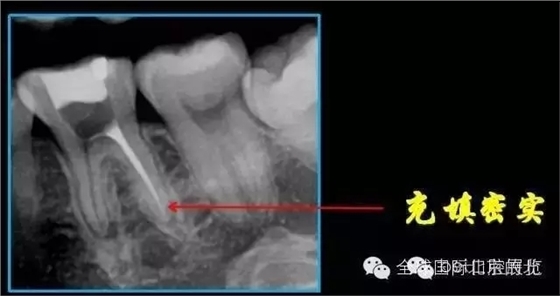

我們再來看看患牙:

X-RAY示:近遠中牙根都有陰影存在,牙周膜都有些許增寬,近中頸部位置牙體有低密度減低影,就是楔狀缺損的位置。 病因分析:楔狀缺損的深齲致牙髓壞死引起的根尖炎癥,應(yīng)囑患者以后改變刷牙方式 診斷:36慢性根尖炎急性發(fā)作 治療方案:36做根管治療,然后充填完成后行冠修復(fù)。 首次治療過程:開髓引流,無明顯滲出液,pathfile疏通根管,沖洗,氫氧化鈣暫封,一周復(fù)查。